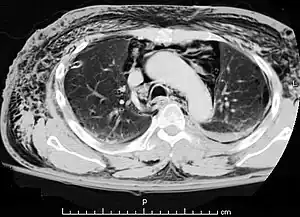

| A CT scan showing air in the mediastinum with subcutaneous emphysema, which can result in Hamman's syndrome | |

Hamman's syndrome, also known as Macklin's syndrome, is a syndrome of spontaneous subcutaneous emphysema[1] (air in the subcutaneous tissues of the skin) and pneumomediastinum (air in the mediastinum, the center of the chest cavity), sometimes associated with pain and, less commonly, dyspnea (difficulty breathing), dysphonia, and a low-grade fever.